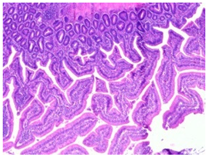

2.4.3. Histopathological Examination

A veterinary histopathologist performed the evaluation in a blinded manner. Ten jejunal samples from 5 replicates of each group (Control vs. SNCE) were routinely fixed in 10% neutral buffered formalin, embedded in paraffin (Paraplast, Sigma-Aldrich, Saint Louis, MO, USA), and subsequently cut on a rotatory microtome. Preparations of 4 µm thickness were automatically stained with hematoxylin and eosin (HE, Varistain Gemini Thermo Scientific, Winsford, UK).

The microscopic analysis of HE slides was carried out with a BX43 light microscope equipped with an SC30 digital camera (Olympus Optical, Hachioji, Japan). Pictures were analyzed and recorded by computer software (CellSens Entry 2011V4.3.1, Olympus Lifescience, Tokyo, Japan). The presence of pathological changes was observed.

The histopathological examination figures from one representative sample per group are presented in Table 9.

Table 9.

Histopathological observation of jejunum from CTL and SNCE group.

Histopathological observations showed that the jejunum samples from the SNCE group were characterized by scant inflammatory cellular infiltrates while the inflammation was severe in the CTL group (Table 9). Moreover, connective tissue hyperplasia was visible within the mucosa in the control group compared to the SNCE group. In addition, goblet cells from the SNCE group were strongly filled with mucus compared to goblet cells from the SNCE group. To finish, numerous mitotic figures were observed in samples from the SNCE group compared to the control group in which single or no mitotic figures were observed.

Thirdly, histopathological observations were performed on jejunal samples. These findings are in accordance with our previous results on TEER, confirming that the increase in TEER value in the CTL group was correlated with an inflammatory process in the gut. It is well known that multiple environmental factors, such as changes in feed formulation or high-energy diets, can initiate gut inflammation [43,44]. The reducing effect observed from SNCE may be explained by SNCE composition. Indeed, it has been demonstrated in our previous study that SNCE is mainly composed of pectic oligosaccharides and citroflavonoids [18]. Some of the compounds identified are well described for their beneficial effect on different gut compartments, including anti-inflammatory properties. For instance, Parhiz et al. (2015) showed that hesperidin treatment allows for a decrease in the prevalence of inflammatory mediators, including COX-2, iNOS, and NF-κB [45,46]. Eriocitrin and citric acids [47] are also well described for their anti-inflammatory properties. Altogether, these results support the concept that SNCE enhances intestinal health by improving nutrient absorption and gut integrity, which results in an increase in broiler chickens’ growth performance.